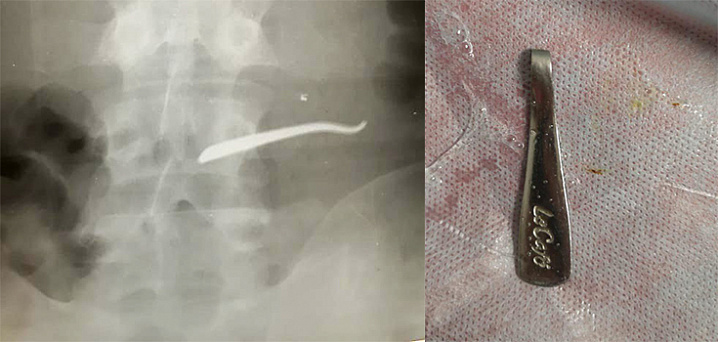

Врачи достали из жителя Мытищ ложку, которую он проглотил на спор

Фото: mz.mosreg.ru